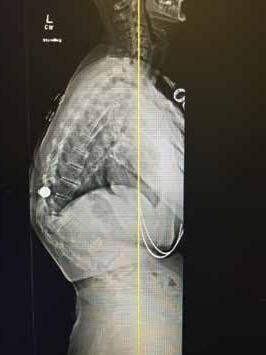

TOTAL DISC REPLACEMENT? TOTAL DISC

Total disc replacement (TDR) may be an alternative to spinal fusion for patients with cervical or lumbar herniated discs or degenerative disc disease.

The goals of total disc replacement surgery are to maintain segmental spinal motion, relieve pain, increase activity, restore disc height and proper spine curvature, and reduce post-operative recuperation time.

If you are experiencing neck or back pain and are considering surgery, isn't it worth your time to schedule an appointment with Dr. Jason E. Garber to nd out if motion preservation technology is an option for you?

Dr. Garber is one of Southern Nevada's most experienced spinal surgeons and a leader in arti cial disc replacement surgery.